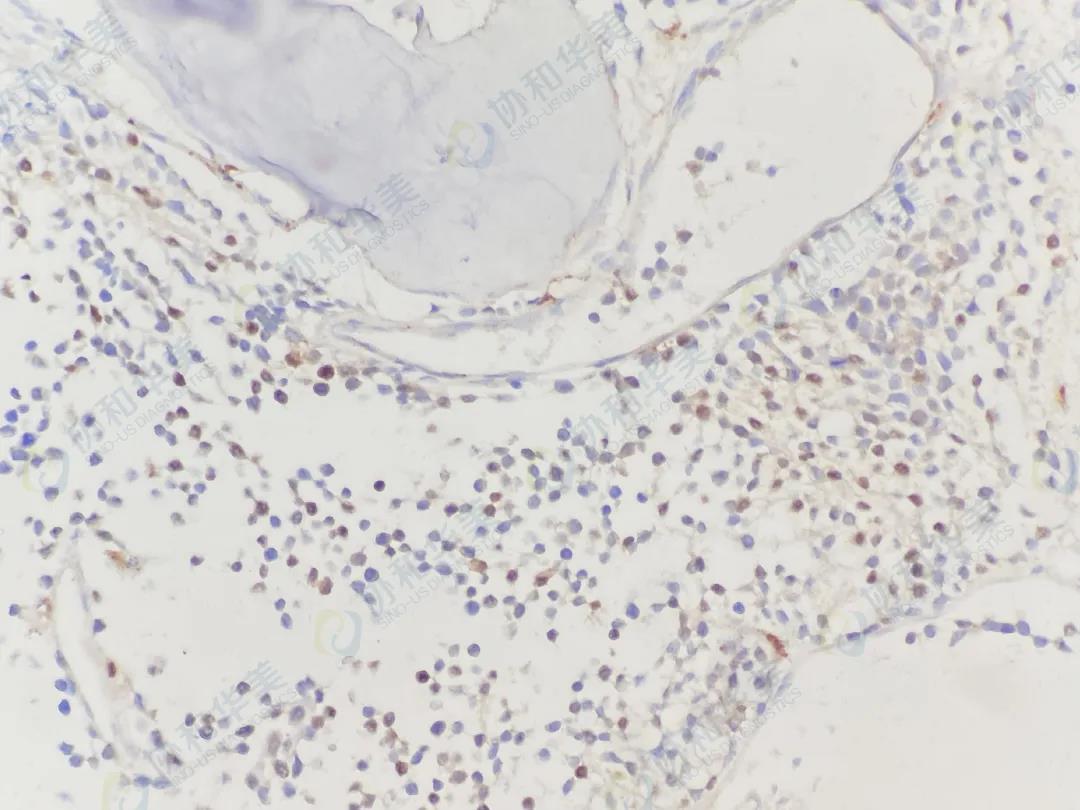

CD56                                                 Desmin